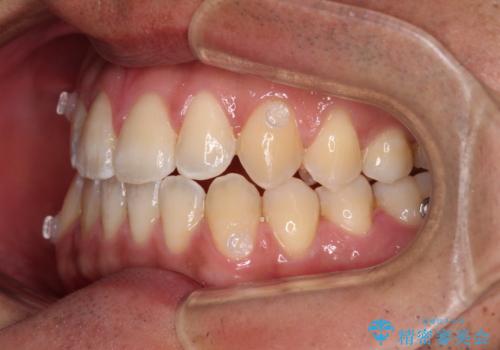

- 前歯のデコボコを気にして来院された患者様です。

歯列としてはワイヤー装置でもインビザラインでも対応可能でしたが、インビザラインが苦手とする上顎側切歯(真ん中から2番目の歯)の舌側転位が顕著でした。

治療の確実性を上げるために、インビザライン開始前に上顎のワイヤー装置にて舌側転位を解消し、その後インビザラインにて矯正治療を行うこととしました。

前歯のデコボコが早めに改善され、スムーズに治療を終えることができました。